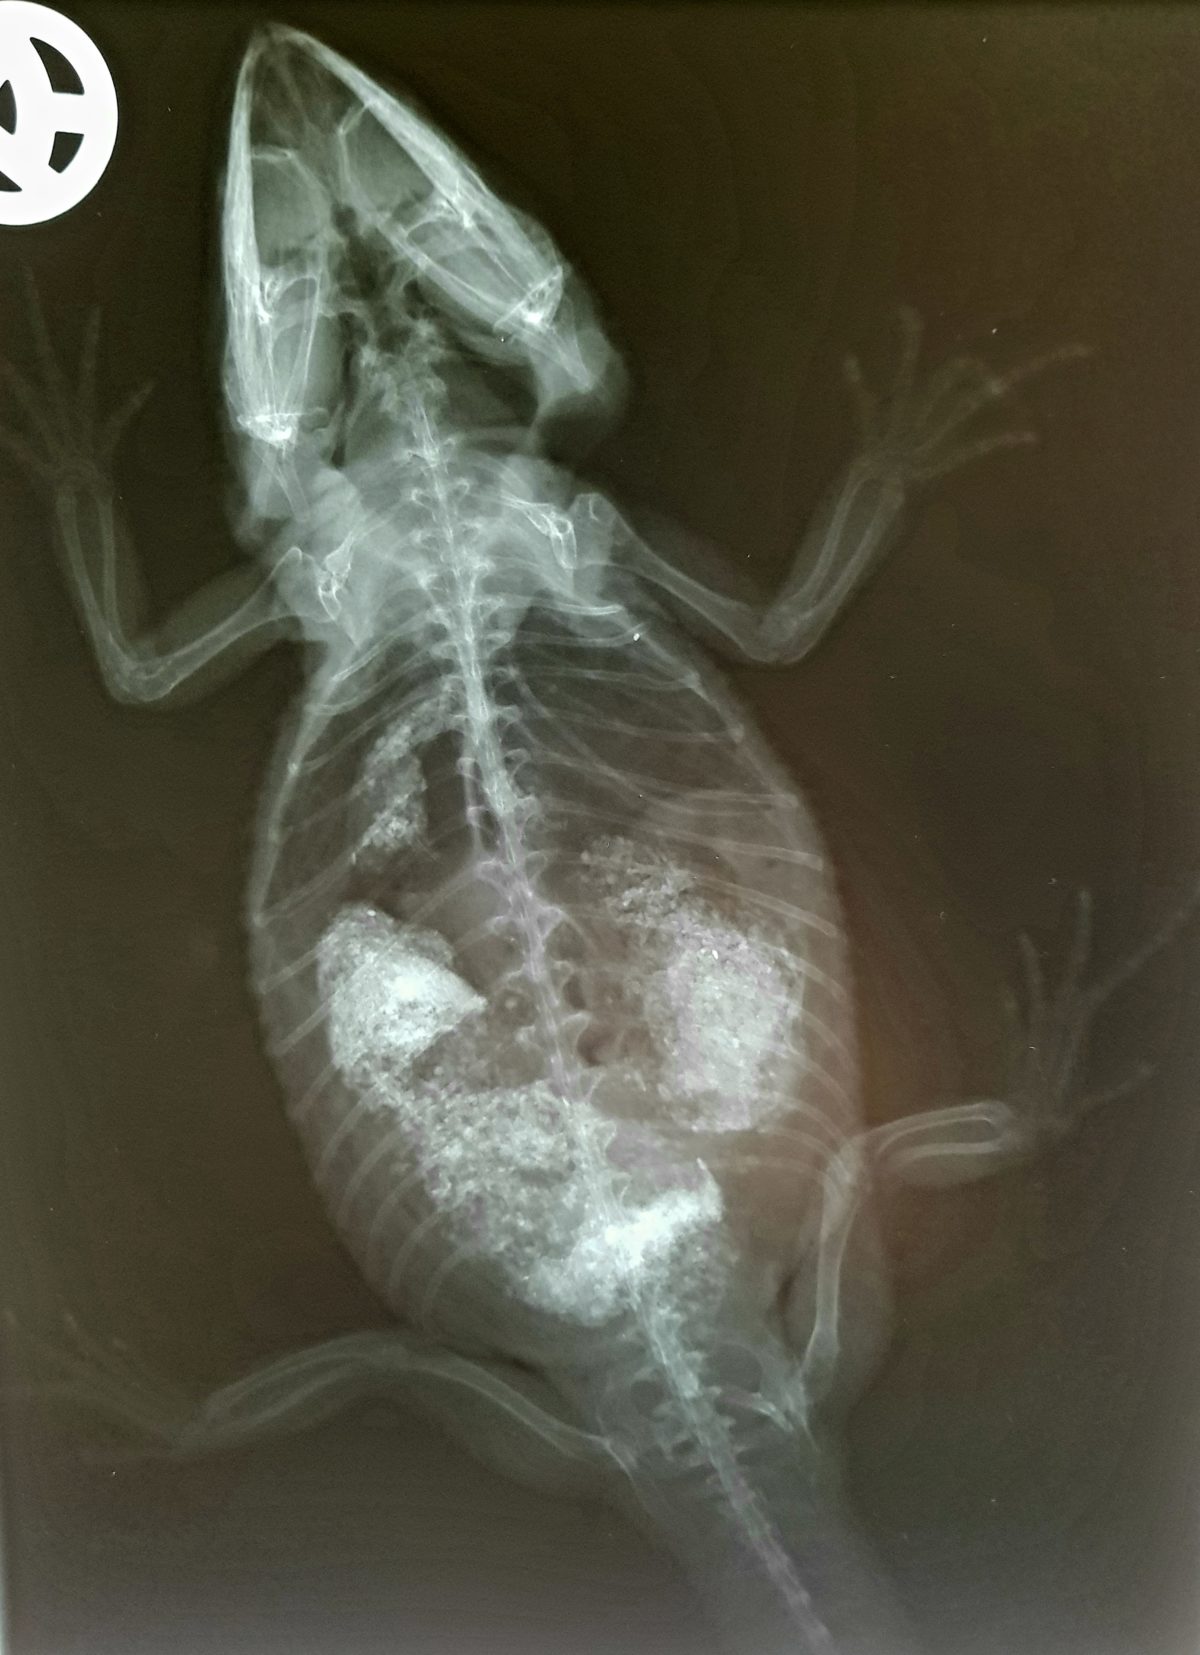

Arttypische Krankheiten Bartagame - Kleintier, Vogel Und

bartagame krankheiten bartagamen eier legen.